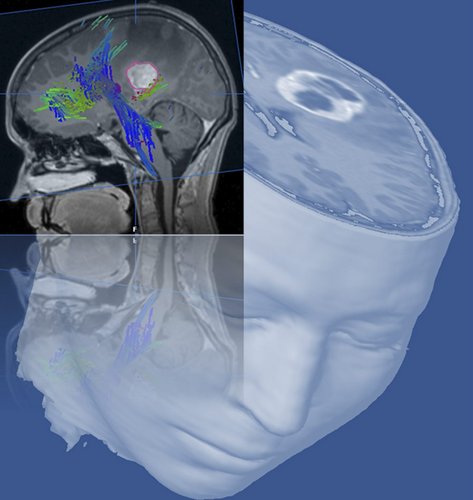

Einen besonderen Schwerpunkt beider Kliniken stellt die Therapie von Hirntumoren dar, deren Diagnosestellung das Leben der Betroffenen oft schlagartig verändert. „Der rasante Fortschritt in der Medizintechnik ermöglicht uns jedoch, dass wir Tumoren immer häufiger und auch präziser entfernen können“, sagt Prof. Wirtz und ergänzt: „Dabei gelingt es der modernen Neurochirurgie mittlerweile gut, die durch die Operation verursachten neurologischen Störungen zu minimieren oder sogar ganz zu vermeiden.“

„Und auch im Bereich der Strahlentherapie haben Fortschritte und technische Weiterentwicklungen die Behandlungsmöglichkeiten von Patienten mit Hirntumoren deutlich verbessert“, führt Prof. Wiegel aus. „Mit Hilfe der so genannten intensitätsmodulierten Strahlentherapie (IMRT) lässt sich zum Beispiel das gesunde Hirngewebe viel besser schonen. Nebenwirkungen, vor allem Spätfolgen der Therapie, können so besser vermieden werden.“